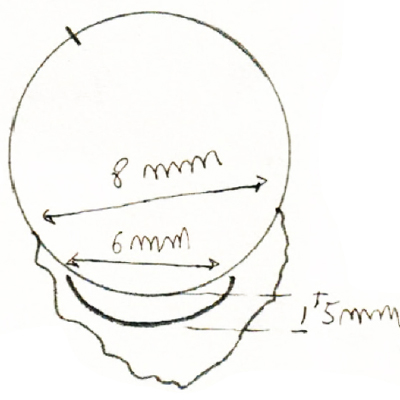

Se extrajo el aguijón bajo anestesia general teniendo la pupila en miosis; con prisma de gonioscopía se localiza el aguijón a las 6:30 en el ángulo y se extrae haciendo incisión conjuntival por desinserción conjuntival limbar inferior de 4 a 8 , paracentesis con aguja de Bowman a cámara anterior a las 11; Delimitación de la incisión escleral con forma arciforme a 1.5 mm del limbo y de 6 mm de cuerda con cauterio; incisión escleral a todo espesor, se levanta el colgajo esclerocorneal y se separa el reborde escleral con espátula plana, y con pinza de Von Mandach se extrae el aguijón. Se cierra con 2 puntos esclerales con Nylon 10-0 , nudos sobre esclera distal al Limbo. Burbuja de aire en cámara anterior a través de la paracentesis y cierre conjuntival con 2 puntos de Nylon 10-0 en los extremos de la desinserción. - Garamicina y Decadrón intraTenonianos. (Foto No23 - aguijón Foto 24 diagrama)

Foto 23 - Aguijon aserrado que fué extraído

Foto 24 - Diagrama de la técnica quirúrgica